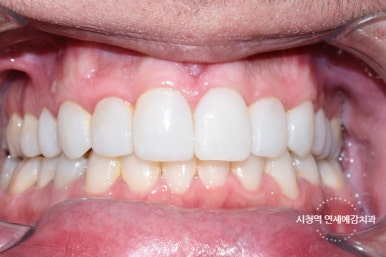

Case 1.

깨진 앞니 레진치료 전후

치아 2개가 깨져있는 상태였는데 환자분이 적게 깨진 치아말고 더 많이 깨진 치아만 치료를 원하셔서

레진으로 진행했습니다.